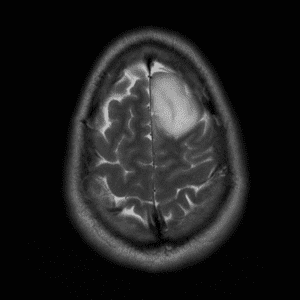

Brain Tumor Practice Cases

Case #2

Cavernous malformation